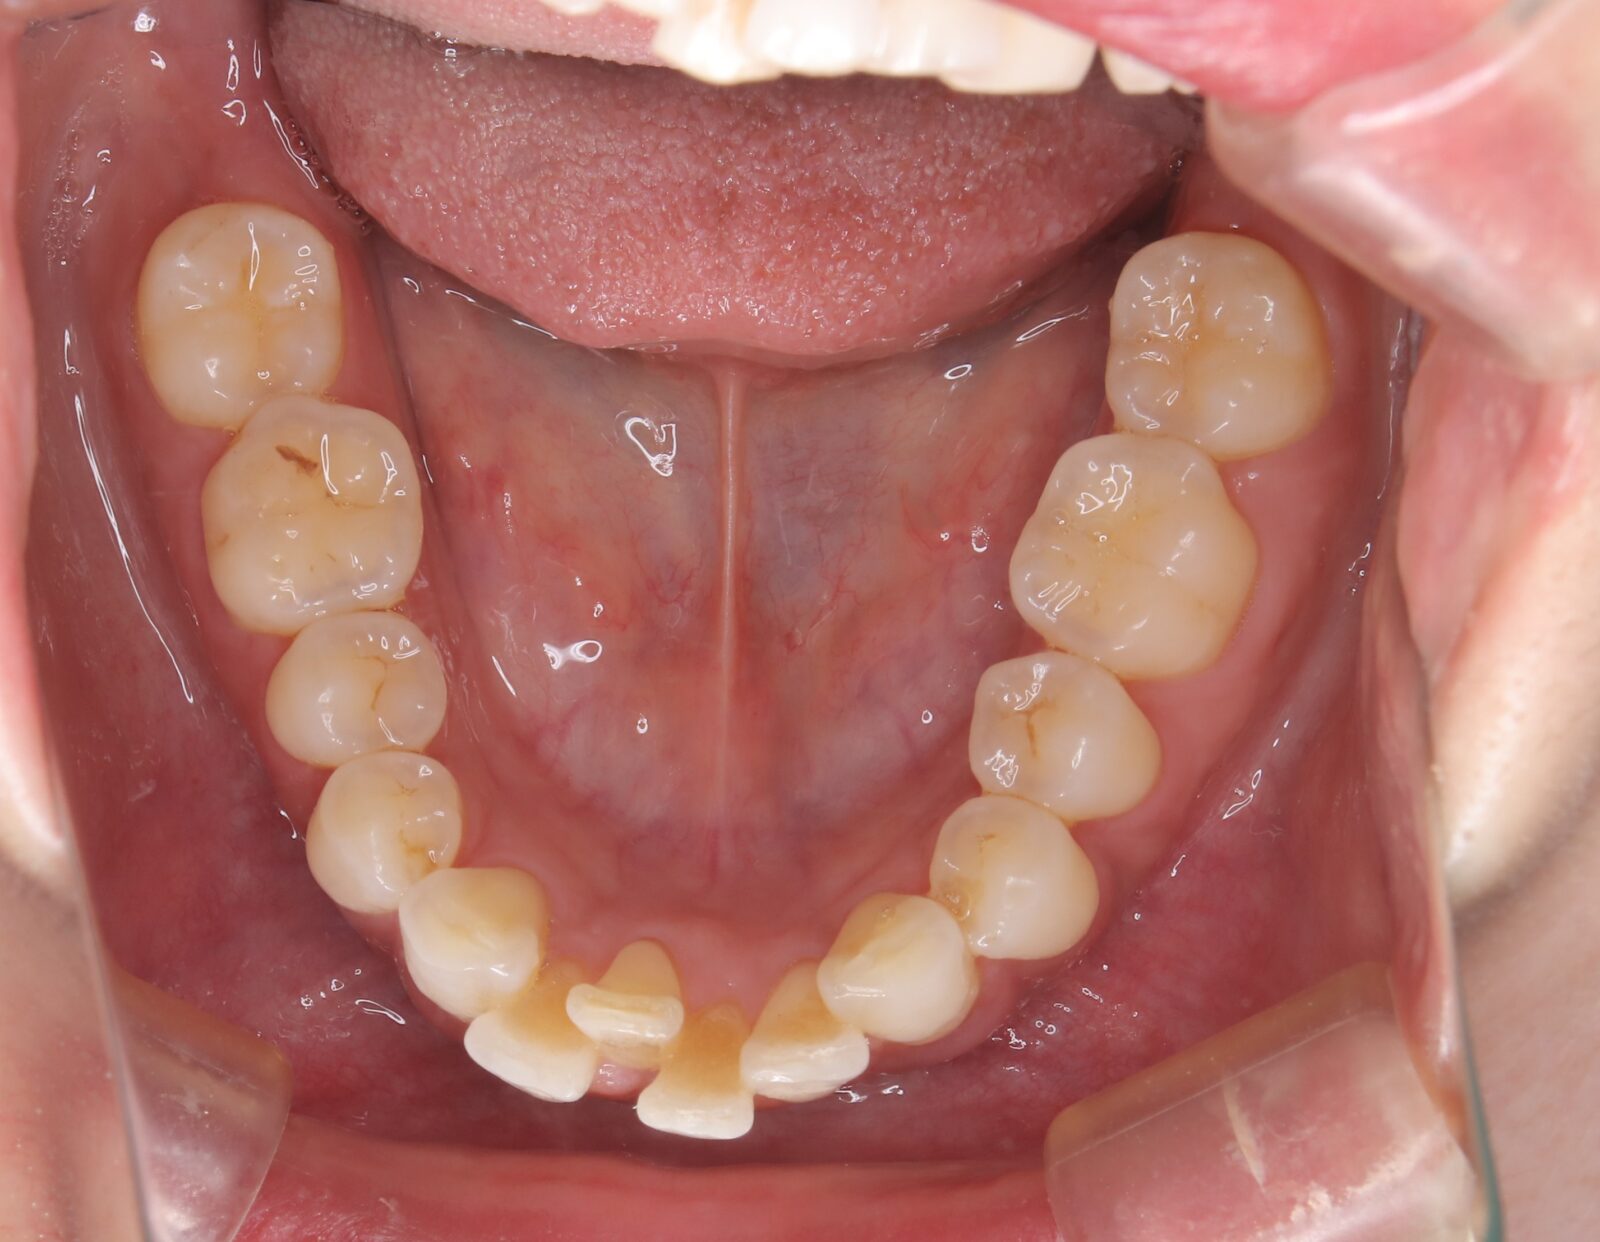

インビザライン(全体矯正)+ホワイトニングコースの症例

歯の裏に歯が隠れてしまっていたため、全体矯正(非抜歯+遠心移動)で美しく改善。

・費用:935,000円(税込)

・治療期間:30ヶ月

・通院回数:30回

・35歳女性

-リスクと副作用-

・長時間マウスピースを装着するため、むし歯や歯周病のリスクがある。治療後はリテーナーを装着しないと後戻りしてしまうリスクがある。

・ホワイトニング剤の影響で知覚過敏が起こる可能性がある。色が徐々に戻る可能性がる。